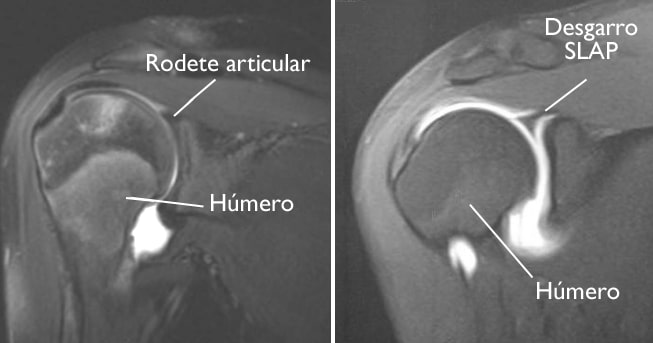

(Izquierda) MRI de un hombro sano. (Derecha) Esta MRI muestra un desgarro en el rodete articular.